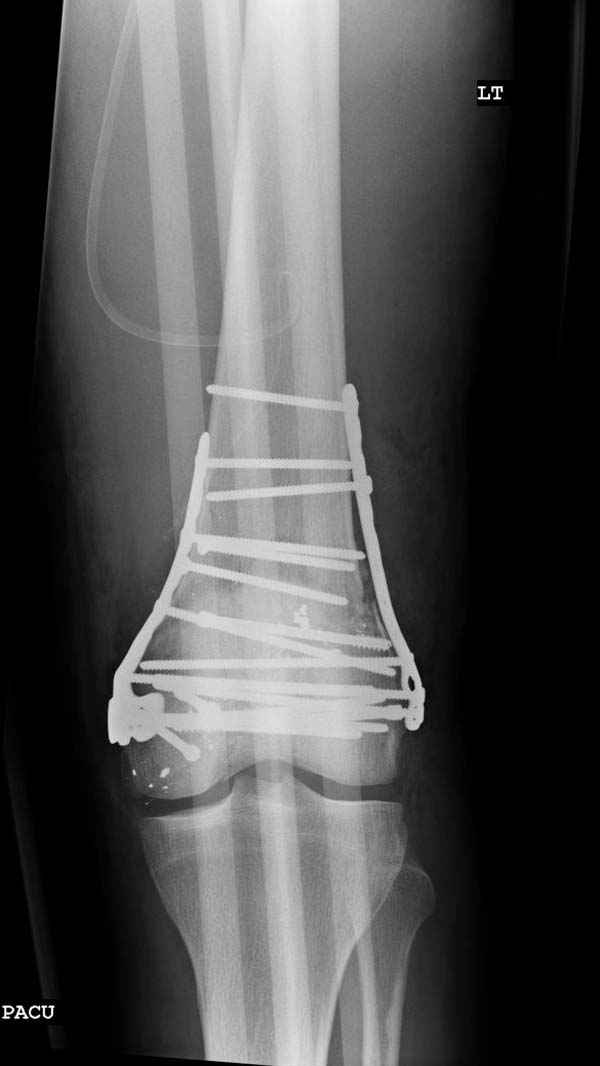

По Густило и Андерсену все high-energy переломы являются III не зависимо от степени повреждения мягких тканей. Plating такого перелома на второй день кажется немного рискованным хотя "победителей не судят". Судя по КТ, медиальный мыщелок стабильный, насколько необходимо было его фиксировать?

Красиво и быстро?! - две пластины + 18 шурупов.

Идеальная репозиция?! -На снимочке A-P проeкции видна "зазубрина" по суставной поверхности, латеральный снимок - тоже не идеально.

Множество мелких FB в кости.